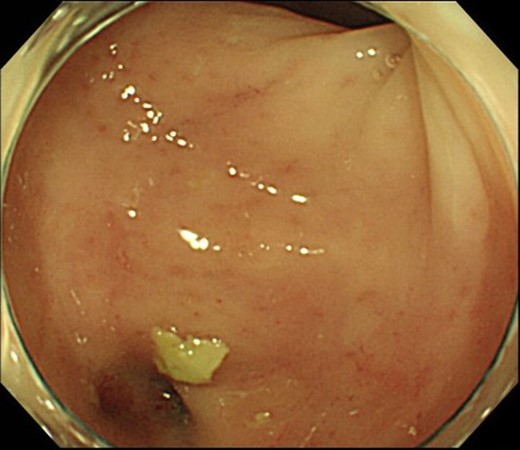

Case 1 was a 71-year-old man with a BMI of 29.7 kg/m2. Laparoscopic low anterior resection (LAR) and ileostomy was performed for rectal cancer in 2017 years. Postoperative fever and lower abdominal pain were noted, and colonoscopy was performed, and anastomotic leakage was noted with a correction of about 1/2 around the 6 o’clock direction of the anastomotic region, and fistula and formation of a large abscess cavity. After identification (Fig. 1), a tube was inserted for drainage and conservative treatment was performed. The patient was discharged on POD 46. Four months after the operation, marked improvement in the abscess cavity was noted but still remained (Fig. 2a and b). Anastomotic leakage was almost improved by colonoscopy at 17 months after surgery, but at the preference of the patient we performed colostomy 22 months after surgery (Fig. 3). It took a long time to improve intestinal movement of the colon because the large intestinal tract had not been used for a long time, and conservative treatment was performed using a nasogastric tube for paralytic ileus. Diet was initiated 7 days after surgery, and the patient was discharged from the hospital 14 days after surgery. The Wexner score [2] was 19 points one month after closure, 17 points 3 months after the operation and 16 points after 6 months after the operation, and severe anal dysfunction was observed, but gradually improved.

(a) Colonoscopy shows a fistula (arrow). (b) Enema examination shows a cavity (arrow) leading from the fistula.